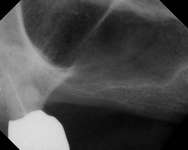

Figure 3A Ridge-split osteotomy with lateral wall expansion. Figure 3B Particulate bone graft was applied, and simultaneous implant placement was performed. Figure 3C The site was covered with barrier membrane.

Figure 3D The site 6 months after surgery, confirming integration. Figure 4A Preoperative radiograph showing ridge resorption.